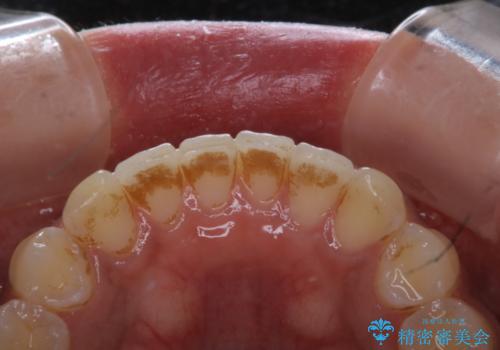

- フロスが以前よりも通りずらくなり、クリーニングしてほしいとのことでした。歯科医院でのクリーニングは3年ぶりとのことです。PMTC60分コースを行いました。

歯科医院で行なわれる専門家による徹底した歯面清掃をPMTC(Professional Mechanical Tooth Cleaning)といいます。専用の機器とフッ化物入り研磨剤を使用して、歯みがきで落とせない歯石や磨き残したプラークを中心に総ての歯面の清掃と研磨を行ない、齲蝕や歯周病になりにくい環境を整えます。

歯石が溜まると、歯と歯の間が埋め尽くされてしまい、デンタルフロスが通りずらくなったり、通せなくなります。